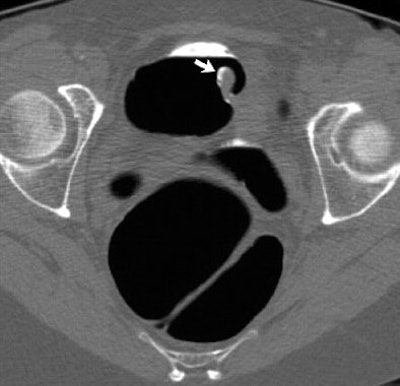

| Inverted appendiceal stump in 63-year-old asymptomatic woman. Prone transverse (B) 2D images from CTC confirm pedunculated lesion (arrow) detected on 3D view and show its soft-tissue composition. Lesion is located at or near appendectomy site, but this does not completely exclude possibility of neoplasm. Image republished with permission of the American Roentgen Ray Society (AJR 2006; 186:535-538). |

The patient described above was referred for routine colorectal screening with VC. Her surgical history was significant only for remote appendectomy. She underwent standard bowel preparation of oral sodium phosphate (45 mL), 2% barium sulfate suspension (250 mL), and water-soluble iodinated contrast material (diatrizoate, 60 mL) the day before the exam.

Supine and prone CT images were acquired on a MDCT scanner (LightSpeed Ultra, GE Healthcare, Chalfont St. Giles, U.K.) using an 8 x 1.25 detector configuration, 1-mm reconstruction interval, 120 kVp, and 50 mAs. The study was interpreted by an experienced gastrointestinal radiologist using V3D Colon software (Viatronix, Stony Brook, NY). Primary 3D interpretation with 2D correlation of suspicious findings was used to interpret the results.

CT findings revealed a 10-mm pedunculated polypoid lesion at the medial base of the cecum. No additional findings were identified, but despite the surgical history and location of the lesion, "a neoplastic polyp could not be confidently excluded," the authors wrote. The patient was referred for conventional colonoscopy, which was negative.

"The endoscopic appearance of the polypoid cecal lesion was thought to be most compatible with an inverted appendiceal stump," the authors wrote. Biopsies revealed benign colonic mucosa with underlying lymphoid tissue.